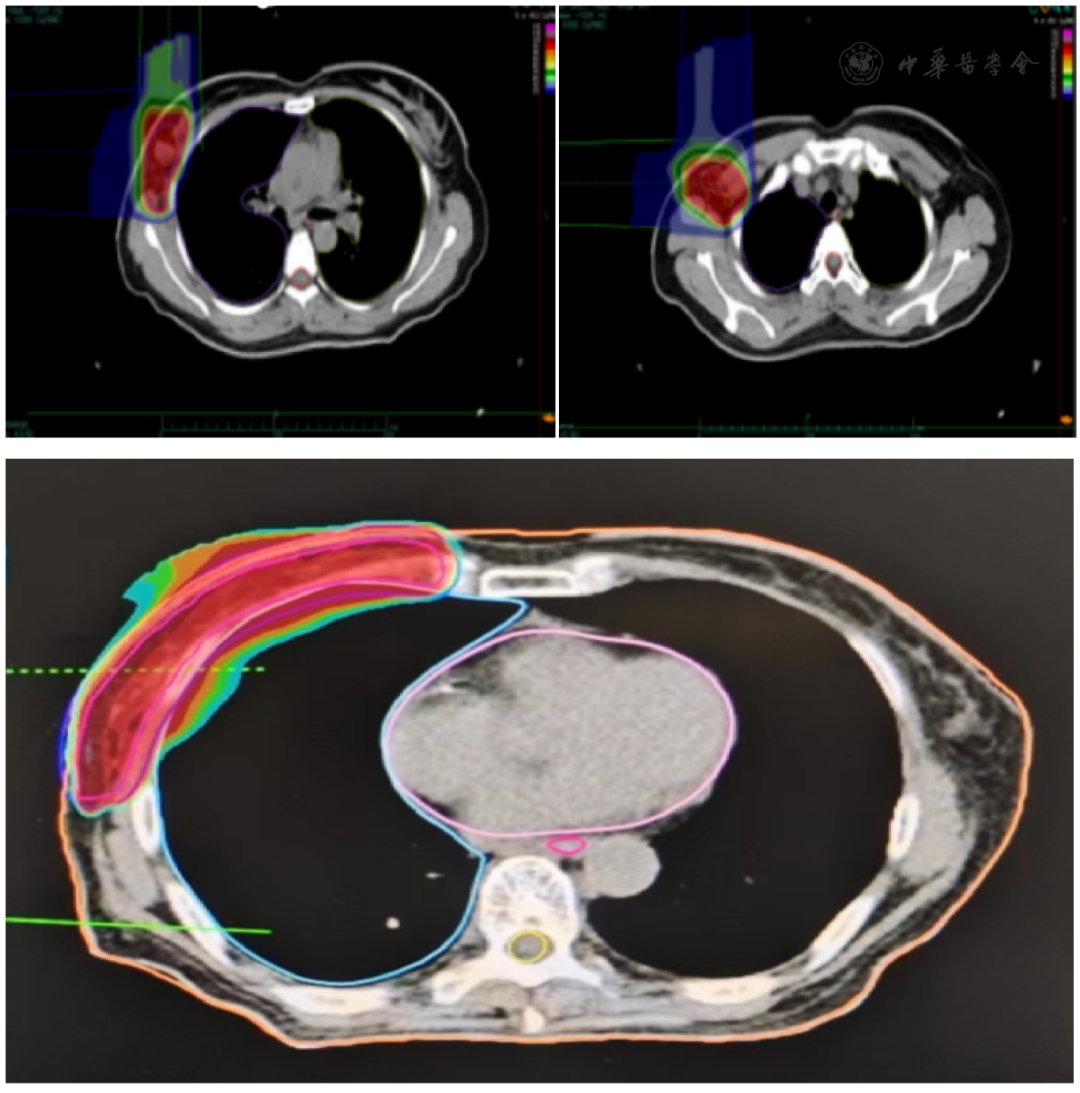

患者拒绝手术并入院就诊,给予右乳肿物,右侧腋窝转移淋巴结、右侧胸壁、右侧腋窝及锁骨淋巴结引流区碳离子治疗,剂量为72 Gy(RBE)/12Fx( 图1 , 图2 )。

图1 剂量云图 A:原发灶剂量云图;B:腋窝淋巴结剂量云图;C:胸壁剂量云图

具体放疗计划为:GTVt为右乳病灶,GTVn为右侧腋窝转移淋巴结;CTVt(GTVt+0.5 cm),CTVn(GTVn+0.5 cm),CTV(CTVn+CTVt+右侧胸壁、右侧腋窝及锁骨淋巴结引流区),右侧胸壁上界为乳腺组织最上缘约2 cm并与锁骨上/下野接衔,下界为乳房褶皱下2 cm,后界包括1 cm肺组织,前界为乳房前界,内界为乳房组织内缘;外界与腋窝野衔接。锁骨上/下野上界为环甲膜水平,下界与胸壁野接衔,内界为胸锁乳突肌内缘,外界为肱骨头内缘。腋窝野与锁骨上下野及胸壁野接衔,下界在第二肋间,外界包括肱骨颈。PTV(CTV+0.5 cm),PTV【48Gy(RBE)/12Fx】,PTVn【60Gy(RBE)/12Fx】,PTVt【72Gy(RBE)/12Fx】;90%的PTV满足90%的处方剂量。危及器官剂量受量为:食管【Dmax=1.9Gy(RBE)】,右肺【D20%=1.5Gy(RBE)】,脊髓[Dmax=0.3Gy(RBE)]。综合治疗方面,患者拒绝化疗,根据CSCO乳腺癌指南推荐,对于不耐受化疗、不接受化疗或化疗疗效欠佳的激素受体阳性患者可行内分泌治疗,故给予患者"枸橼酸他莫昔芬片10 mg/次、2次/d"内分泌治疗及"醋酸戈舍瑞林缓释植入剂3.6 mg、皮下注射、每4周1次"卵巢去势治疗。